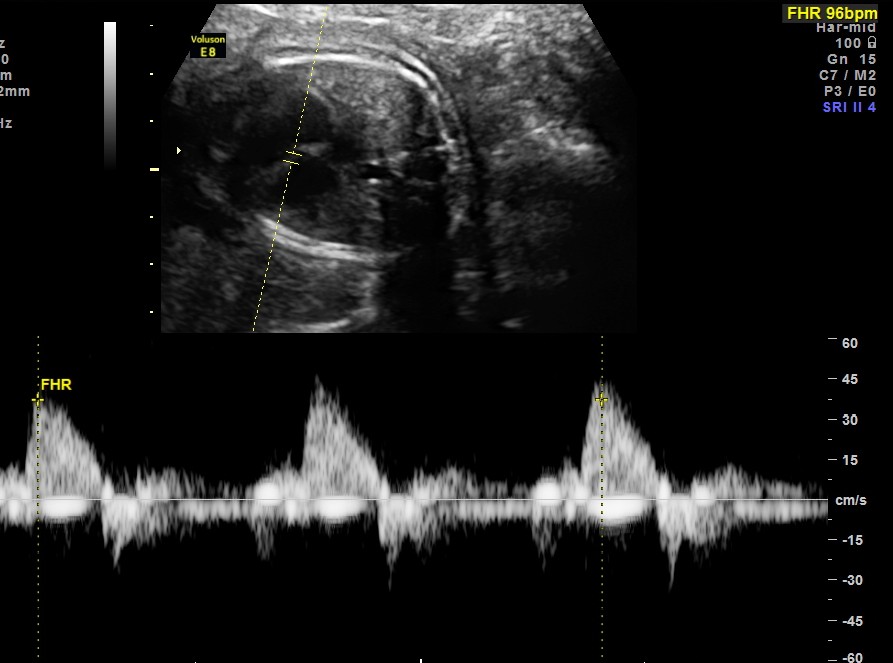

this fetus showed intermittent A.V.DISSOCIATION, BRADYCARDIA AND NORMAL RHYTHM

the following picture shows A.V.DISSOCIATION ( ventricular beats above and atrial below)

ventricular rate( above mid line ) is 96 bpm ;

atrial rhythm ( seen below base line ) shows dissociation